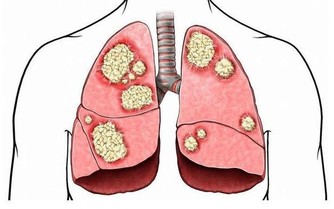

一般我們人體的各項器官在晚上都是要進行休息的,但是有很多人就會選擇在晚上玩手機,從而就會促使大腦或者一些器官仍在繼續工作,處在興奮狀態,長期下去就會擾亂體內的內分泌,從而使得體內的免疫系統也逐漸下降,容易被疾病纏身。